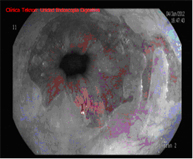

El diagnòstic es porta a terme mitjançant endoscopis d'alta resolució amb magnificació (augment de la imatge), i utilitza tècniques de cromoendoscòpia afegida, realitzades per endoscopistes especialistes en el diagnòstic precoç de les lesiones precanceroses, i la realització de biòpsies que posteriorment són analitzades.

Radiofreqüència amb sistema HALO

El sistema HALO de radiofreqüència és un aparell que permet l'ablació de la mucosa esofàgica fins una profunditat d'1 mm de forma segura i uniforme. L'ablació és una tècnica en la qual s'escalfa el teixit fins que deixa de ser viable o estar viu. La tecnologia HALO és un tipus molt específic d'ablació en la qual l'energia calorífica s'aplica de forma precisa i controlada. Els assaigs clínics han demostrat que el teixit de Barrett es pot eliminar completament amb la tecnologia d'ablació HALO en el 98,4% dels pacients.